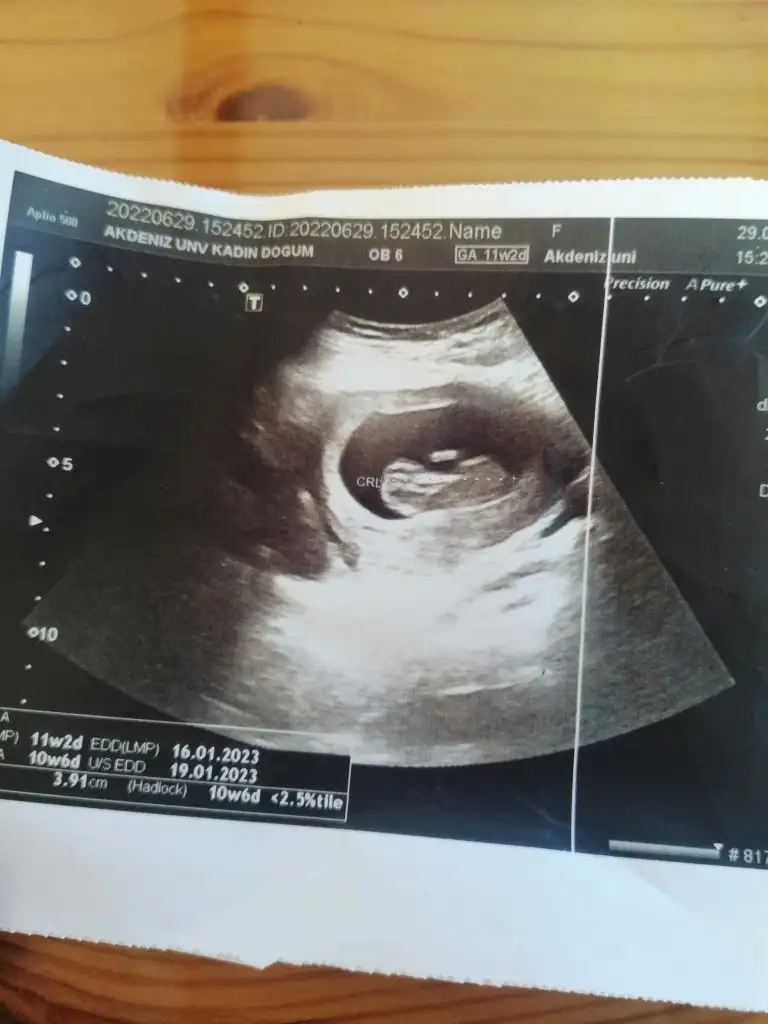

Merhaba ilk gebeligimde doğru tahmin etmistiniz.. Bu ikinci gebeliğim 11 haftalık karindan ultrasonla bakildi cinsiyeti tahmin edebilir misiniz rica etsem

IMG_20220629_162521.webp

:)